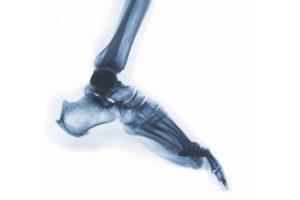

Over the past decades, pronation has been discussed as a potential risk factor for injuries or as the mechanism behind impact damping. However, little is understood about pronation. The objectives of this paper were to (a) define and differentiate between the terms of pronation and eversion, (b & c) underline the importance and problematic aspects ...